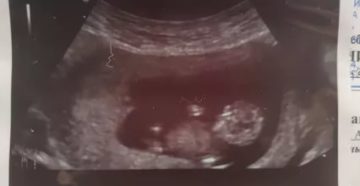

Первый скрининг при беременности: что показывает, когда делают – на каком сроке, каковы нормы и…